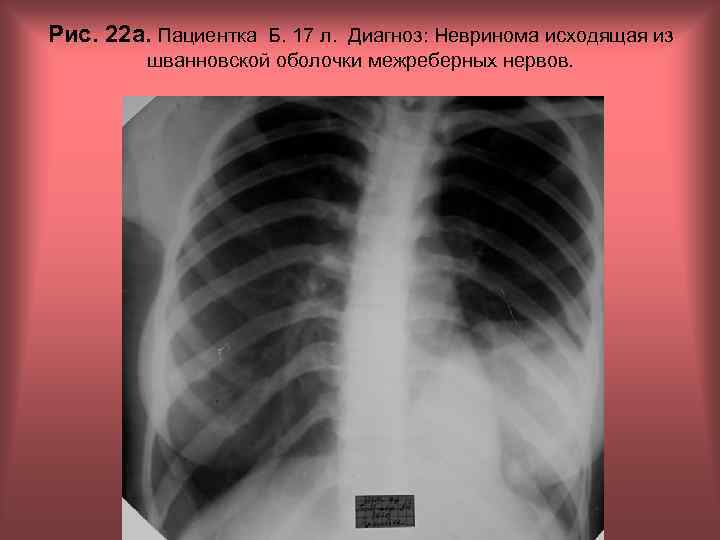

Рис. 22 а. Пациентка Б. 17 л. Диагноз: Невринома исходящая из шванновской оболочки межреберных нервов. Н. С. Воротынцева, С. С. Гольев Рентгенопульмонология

Рис. 22 б. Пациентка Б. 17 л. Диагноз: Невринома исходящая из шванновской оболочки межреберных нервов. Н. С. Воротынцева, С. С. Гольев Рентгенопульмонология

Рис. 22 в. Пациент Б. 17 л. Диагноз: Невринома исходящая из шванновской оболочки межреберных нервов. Н. С. Воротынцева, С. С. Гольев Рентгенопульмонология